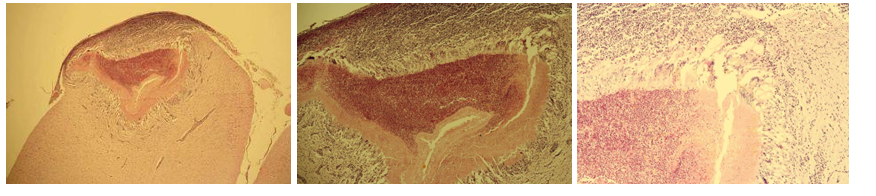

Pericarditis fibrinosa

Description: A layer of thickening edematous subepicaridal tissue and remnant endothelium on the surface of myocardium, covered by fibrinous mass with admixture of lymphocytes and neutrophils. Process demonstrate acute stadium of serosal fibrinous inflammation.

Etiology: Microorganisms such as diphteria, salmonella, sphaerophorus necrophorus

Pathogenesis: Fibrinous inflammation is characterized by exudate containing large amounts of fibrinogen which clots so fibrin is the most conspicuous agent. Fibrin exudation indicates severe acute vascular injury. Occur mostly on mucous and serous membranes. Fibrin can sometimes be reddened by blood and since it is chemotactic, it attracts neutrophils. In cattle, high plasma fibrinogen levels make fibrous exudate more common.

this is?

Cirrhosis hepatis (Hepatitis interstitialis chronica)

Description: Proliferated fibrinous tissue found in the whole section. It is infiltrated by chronic inflammatory cells (lymphocytes, plasma cells, macrophages). Fibrinous tissue originates from interlobular spaces and spreads into the center of the lobules, causing press atrophy of liver parenchyma. Regeneration of bile ducts can be seen in new fibrinous tissue.

Etiology: End-result of necrosis or apoptosis and active inflammation with chronic fibrosis.

Pathogenesis: End-stage diffuse hepatic disease characterized by nodular regeneration with fibrovascular bridging scars containing shunts. Regeneration of tissue leads to formation of variable sized nodules between fibrous connective tissue, distorting the entire liver. In the end, the liver is unable to perform its normal function, and cirrhosis can lead to ascites and hypoproteinemia.